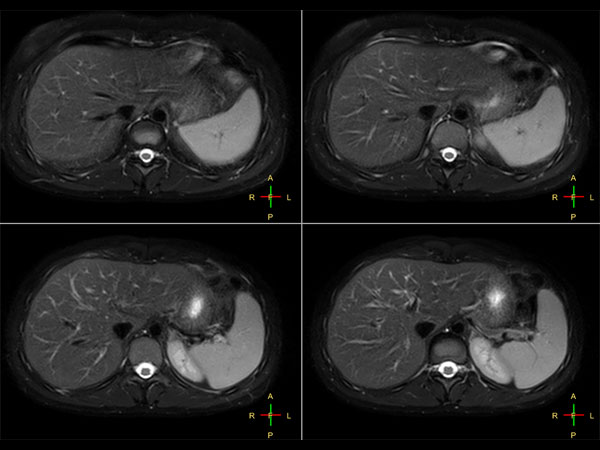

Liver imaging with MultiVane XD